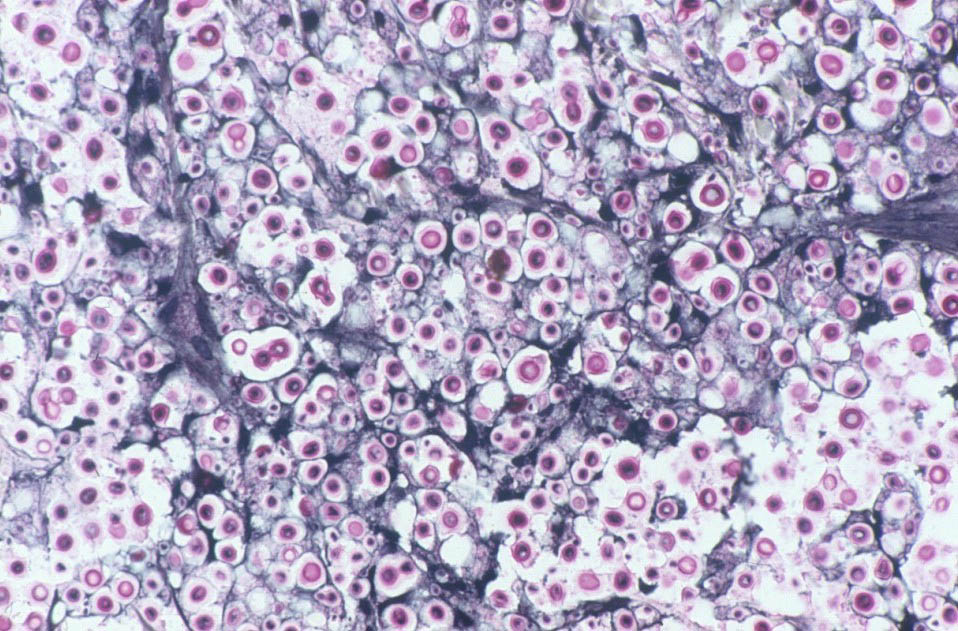

India ink, which outlines the organisms by negative contrast, helps to identify the yeast cells in fluids or macerated tissue samples. In fixed tissue, the capsule of C neoformans may also be stained with mucicarmine, which preferentially stains mucopolysaccharides. Tissue sections can be stained with the Fontana-Masson stain to detect melanin precursors in the yeast cell wall. The presence of melanin or melanin precursors is useful in differentiating C neoformans from other yeasts. |